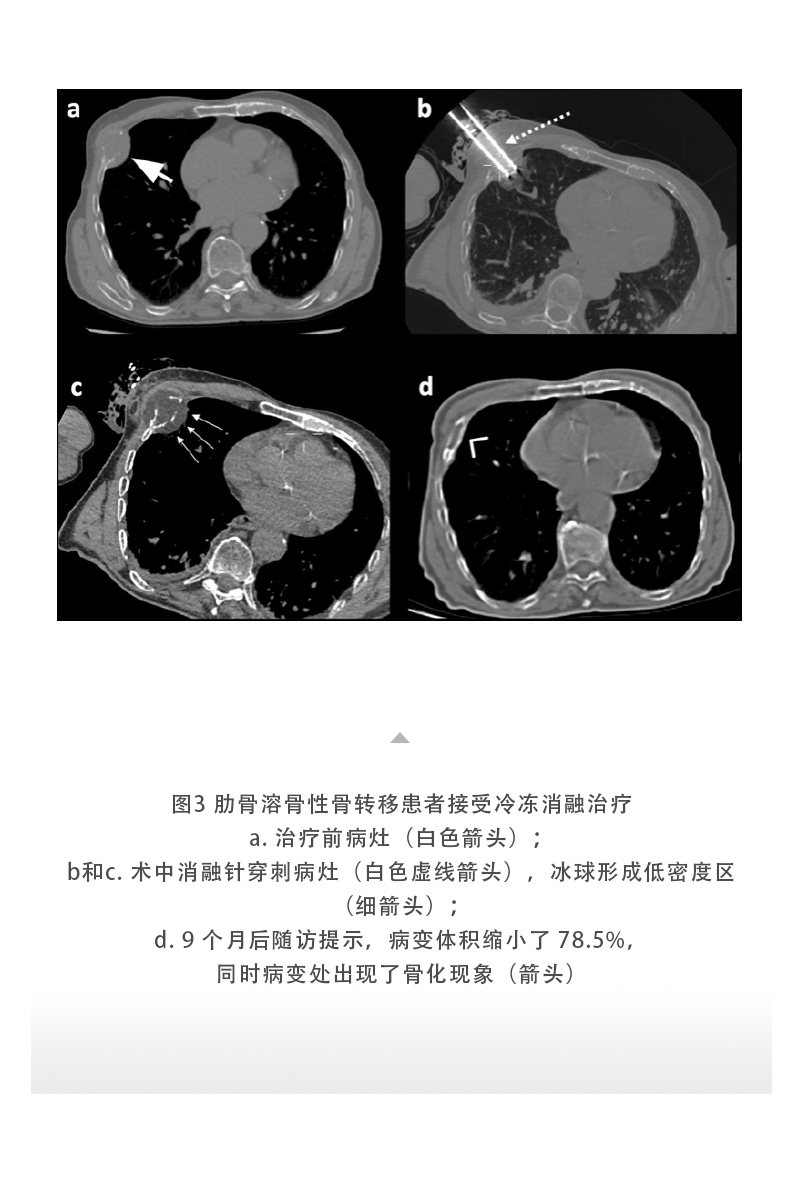

【HYGEA·科研資訊】骨腫瘤冷凍消融